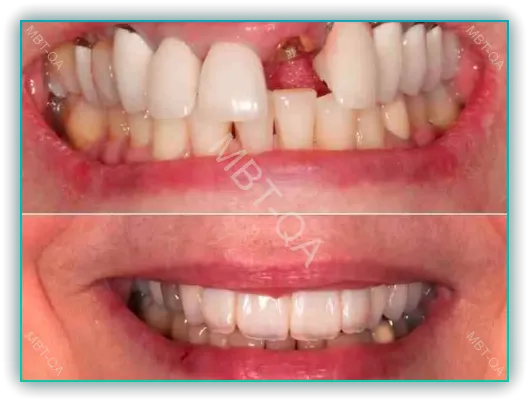

앞니 임플란트는 앞 이빨 상실 시 거의 유일한 대안으로 많이 시술되고 있습니다만 수술 과정에서 몇 가지 문제점이 발생할 수 있습니다.

셋째, 임플란트의 형태가 자연 치아와 다를 수 있어, 이로 인해 심미적 문제가 발생할 수 있습니다. 자연스럽지 않은 모양이나 크기의 임플란트는 입 안에서 부자연스럽게 보일 수 있으며, 이는 환자의 자신감에 영향을 줄 수 있습니다.

앞니 임플란트의 미적 요소는 환자의 만족도에 큰 영향을 미치는 중요한 요소입니다. 임플란트가 자연 치아와 비슷한 외관을 가지지 못할 경우, 이는 환자의 심미적 불만족으로 이어질 수 있습니다.

- 색상 차이와 잇몸 문제: 임플란트와 자연 치아 간의 색상 차이, 잇몸의 색상 변화 또는 임플란트 주변 잇몸의 비정상적인 모양은 심미적으로 불만족스러울 수 있습니다.